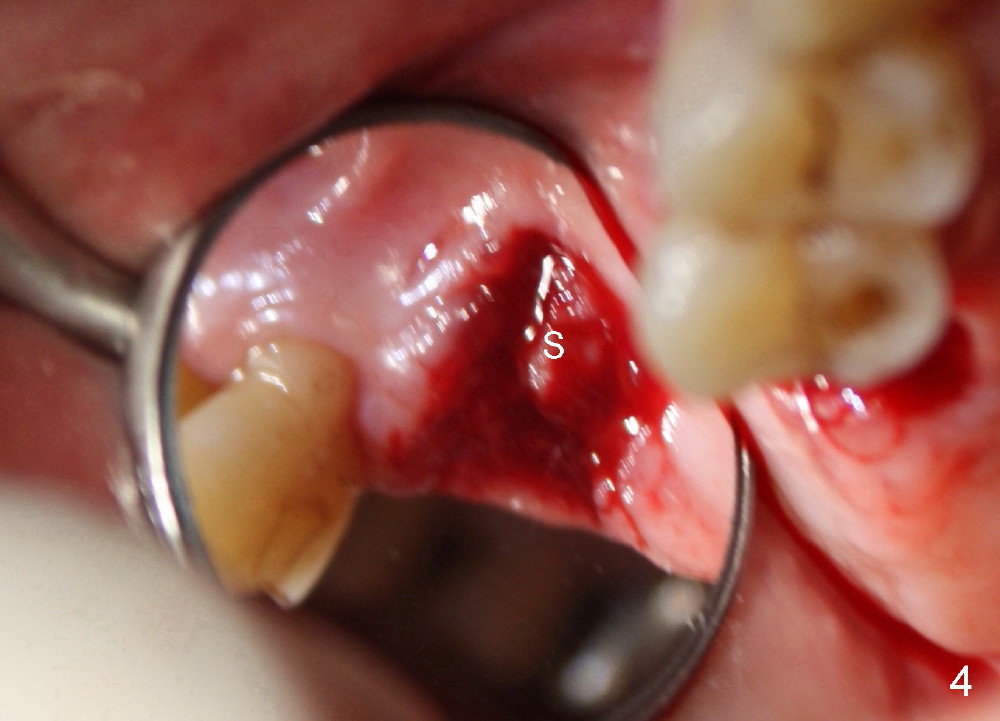

Fig.4 shows the defect post extraction after debridement of infected granulation tissue. Apparently healthy tissue remains undisturbed and attaches to the septum (S).